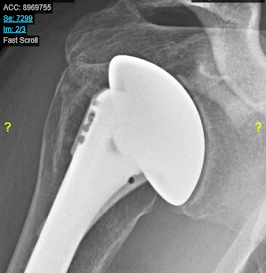

A physically active man presented with pain and stiffness of the right shoulder and these x-rays.

Wishing to avoid the risks and limitations of a conventional total shoulder with a prosthetic glenoid component, he elected a ream and run procedure. He made an excellent functional recovery and returned to full unlimited activity.

He provided a most helpful series of post operative films showing the remodeling of his reamed glenoid.

6 weeks: